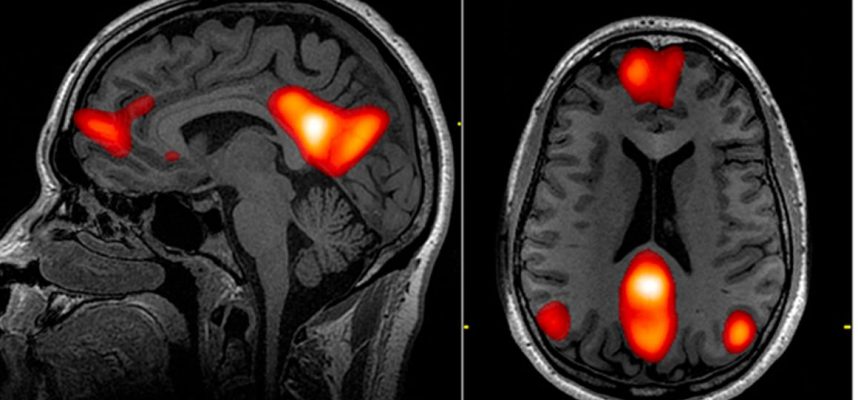

A lokalizált hatásokat tekintve az összes talált rendellenesség egyharmadát a frontális lebenyben találták, az agy azon részében, amely végrehajtó gondolkodási feladatokat lát el, például érvelést és döntéshozatalt. A homloklebeny segít továbbá érzelmeink szabályozásában, viselkedésünk irányításában, és részt vesz a tanulásban és a figyelemben.

“Ezek az adatok azt mondják, hogy a betegek szélesebb körében kell kipróbálni az EEG-t, valamint más típusú agyi képalkotást, például MRI-t vagy CT-t, amelyek lehetővé teszik, hogy közelebbről megvizsgáljuk a homloklebenyt” – mondta Zulfi Hanif, a neurológus és a tanulmány társszerzője. a houloni Baylor Medical College-tól.

“A frontális lebenyt érintő EEG-rendellenességek a COVID-19 encephalopathiában gyakoriaknak tűnnek, és potenciális biomarkerként javasolták őket folyamatos felvétel során” – írják a szerzők cikkükben.